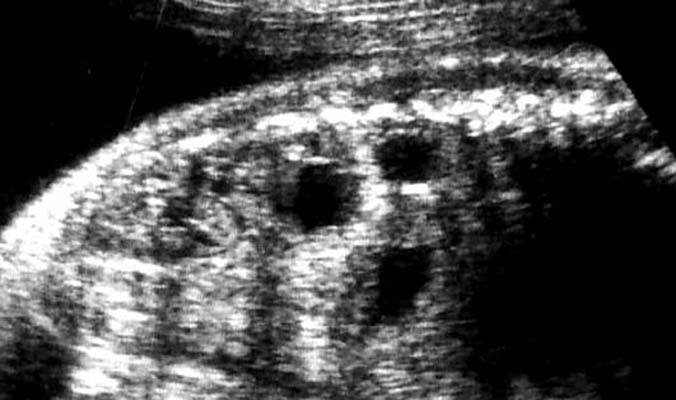

Seques pulm extra-lobaire sous-diph